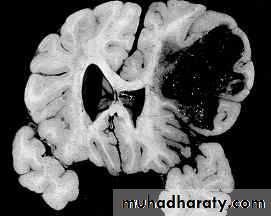

3. Brainstem and hemispheric (Cerebral) Contusion

These are areas of bruising and swellings with intact pia arachnoid, localized or generalized oedema and haemorrhage due to tearing of blood vessels.

3. Cerebral Contusion

Clinical presentations:

1. Prolonged periods of unconsciousness.

2. Focal neurological deficits that persist for longer than 24 hours.

CT scans demonstrates contusions as small areas of haemorrhage in the cerebral parenchyma.

Contusions may resolve with the accompanying deficits or they may persist.